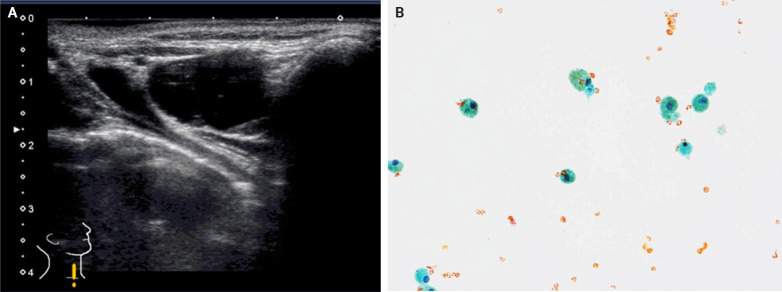

As fine-needle aspiration techniques and diagnostic methodologies for thyroid nodules have continued to evolve and reporting systems have been updated accordingly, we need to be up to date with the latest information to achieve accurate diagnoses. However, the diagnostic approaches and therapeutic strategies for thyroid nodules vary across laboratories and institutions. Several differences exist between Western and Eastern practices regarding thyroid fine-needle aspiration. This review describes the reporting systems for thyroid cytopathology and ancillary studies. Updated reporting systems enhance the accuracy, consistency, and clarity of cytology reporting, leading to improved patient outcomes and management strategies. Although a single global reporting system is optimal, reporting systems tailored to each country is acceptable. In such cases, compatibility must be ensured to facilitate data sharing. Ancillary methods include liquid-based cytology, immunocytochemistry, biochemical measurements, flow cytometry, molecular testing, and artificial intelligence, all of which improve diagnostic accuracy. These methods continue to evolve, and cytopathologists should actively adopt the latest methods and information to achieve more accurate diagnoses. We believe this review will be useful to practitioners of routine thyroid cytology.